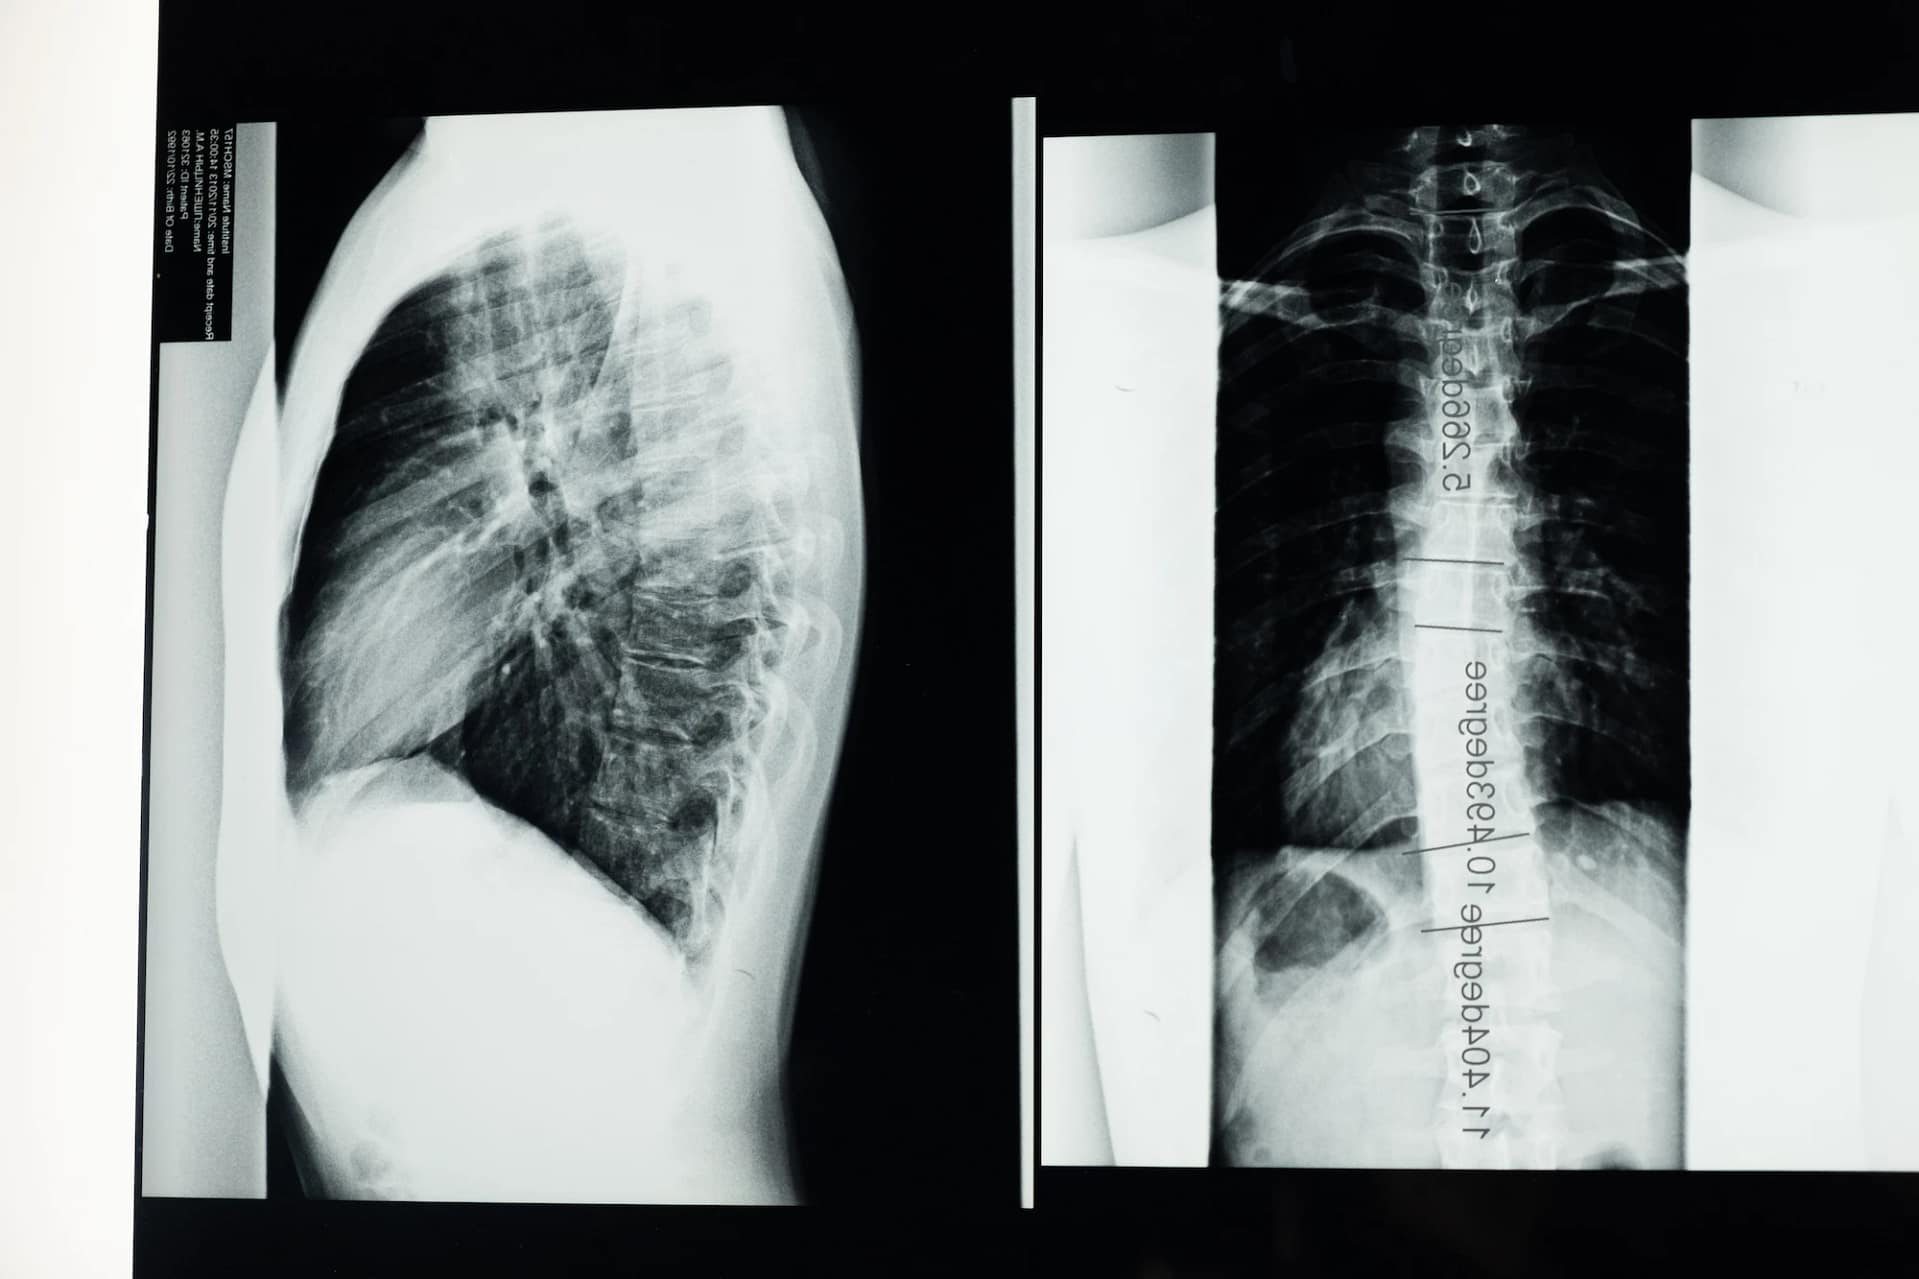

Scoliosis is a progressive, lateral curvature of the spine. When viewed from the side, the spine should have curves. But when viewed from the front, the spine should be straight. Scoliosis can affect both children and adults. Scoliosis is more than 10 degrees of curve, with rotation of the vertebrae.

Types of Scoliosis